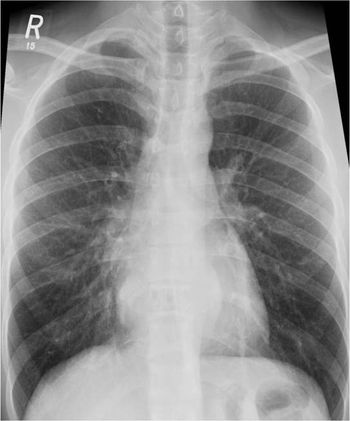

Clinical History: A 60-year-old female with pelvic fracture developed shortness of breath with tachycardia and tachypenea